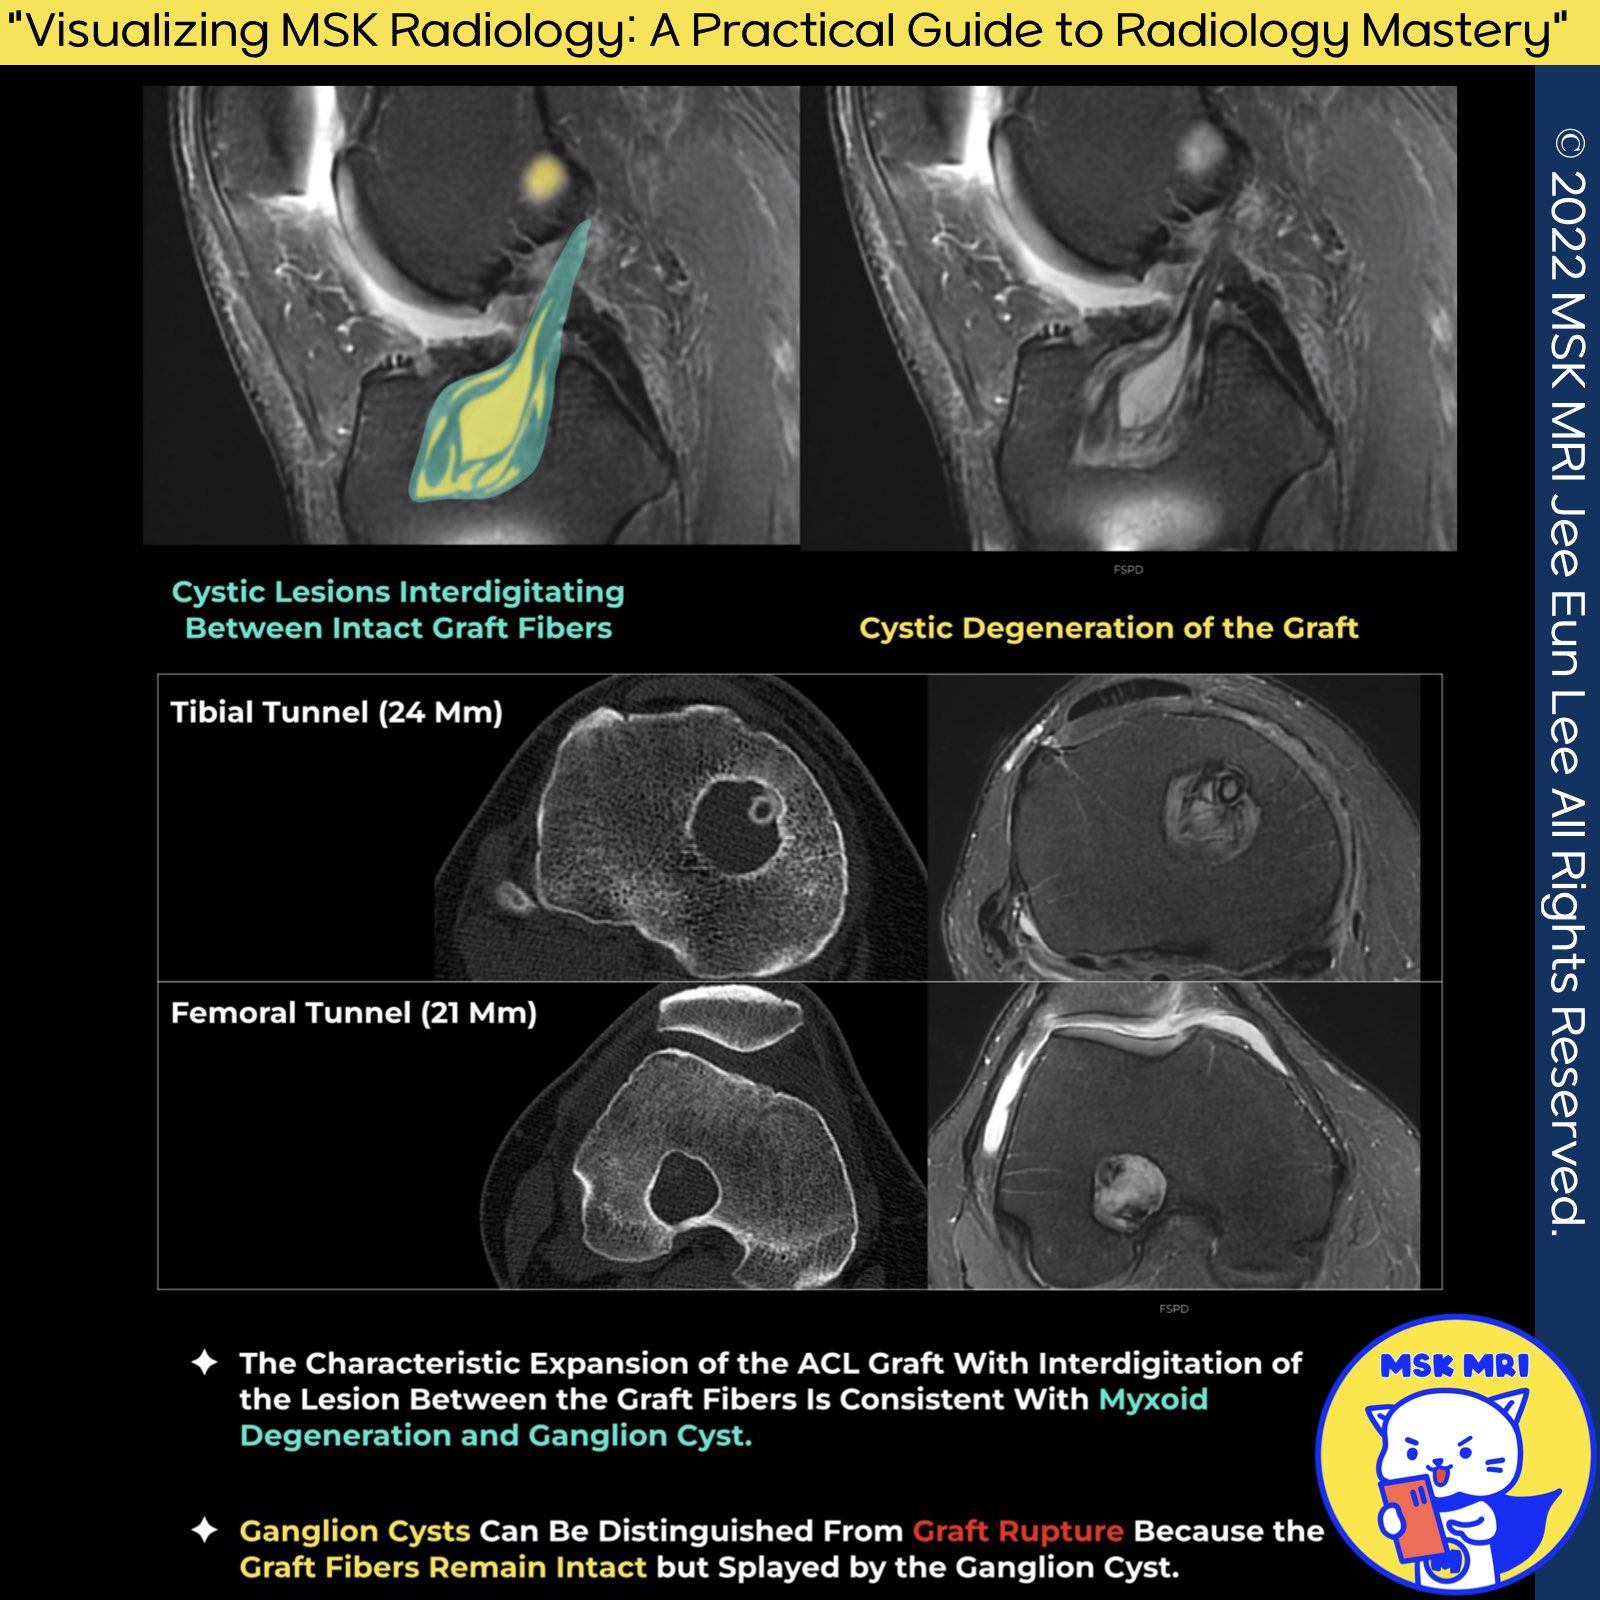

1. Cystic Degeneration of the Graft

- Cystic degeneration, also known as ganglion cyst formation within the graft, is recognized as a late complication of ACL reconstruction.

- These cystic fluid collections can extend proximally through the tibial tunnel into the joint space or distally into the soft tissues anterior to the tibial tubercle (AJR 2010).

2. Ganglion Cyst Formation

- Locations: Ganglion cysts may form within the graft or the tibial tunnel.

- Symptoms: While not associated with graft failure, cysts can be symptomatic due to mass effect, sometimes necessitating debridement or aspiration.

- Complications: Tunnel cysts may lead to pain, graft laxity, and joint instability, with tunnel widening observed.

- Common Associations: Ganglion cysts are more frequently observed with hamstring tendon (HT) grafts and endobutton fixation devices (Skeletal Radiology 2022).

3. Ganglion Cysts vs. Graft Rupture

Distinguishing Features

- Integrity: Ganglion cysts can be differentiated from graft rupture as the graft's fibers remain intact but are displaced by the ganglion cyst.

- Fluid Accumulation: Fluid may gather within the tunnels, particularly within doubled semitendinosus and gracilis tendon grafts, mainly in the first two years post-operation (AJR 2010).